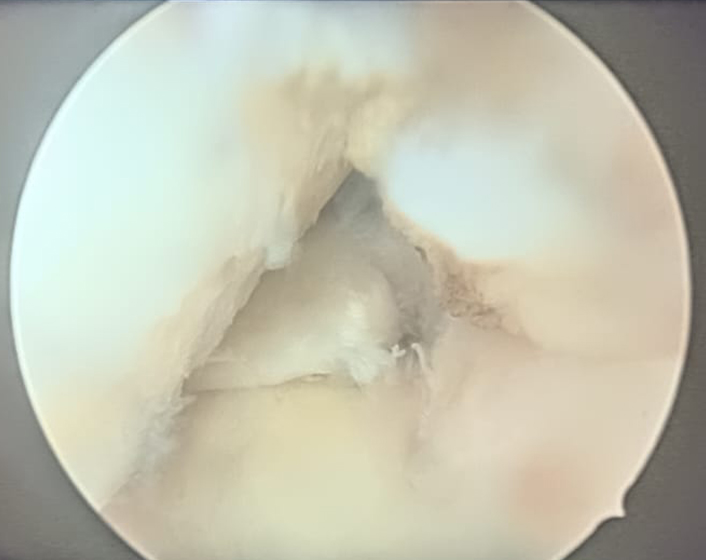

Treatment for a meniscal injury depends on the severity and location of the tear, as well as the patient’s activity level. For minor tears, non-surgical options such as rest, ice, compression, and elevation (RICE), along with physical therapy, can help reduce pain and improve knee function. Physical therapy focuses on strengthening the muscles around the knee to restore stability and mobility. For more severe tears, especially those causing significant pain or locking of the knee, surgical intervention may be necessary. Arthroscopic surgery is commonly used to either repair or remove the damaged portion of the meniscus. In young patients arthroscopic repair is preferred as removal of part or full meniscus increases chances of Osteoarthritis in long term .Post-surgery rehabilitation is crucial for a full recovery and to prevent future injuries.